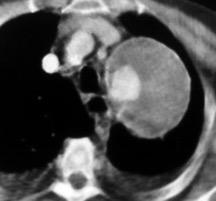

30. DERRAME IZQUIERDO. SÍNDROME DE BOERHAAVE

Rotura esofágica

Laceración transmural espontánea.

Excesos en comida y/o bebida

Marzo 2014: Perforación longitudinal distal secundaria a episodio de vómito (síndrome de Boerhaave). Derrame pleural izdo. que evoluciona a empiema.

Wang C-T et al. Tension hydropneumothorax in a Boerhaave syndrome patient: A case report . World J Emerg Med, 2021. Katabathina V et al. Nonvascular, nontraumatic mediastinal emergencies in adults:a comprehensive review of imaging findings. Radiographics. 2011.